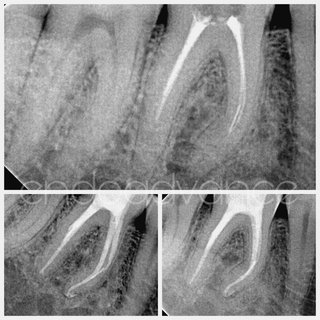

Αρχική ενδοδοντική θεραπεία σε κεντρικό τομέα της άνω γνάθου με δύο ρίζες